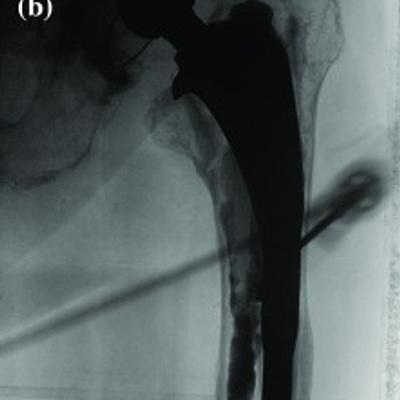

Purpose In orthopaedics, minimally invasive injection of bone cement is an established technique. We present HipRFX, a software tool for planning and guiding a cement injection procedure for stabilizing a loosening hip prosthesis. HipRFX works by analysing a pre-operative CT and intraoperative C-arm fluoroscopic images. Methods HipRFX simulates the intraoperative fluoroscopic views that a surgeon would see on a display panel. Structures are rendered by modelling their X-ray attenuation. These are then compared to actual fluoroscopic images which allow cement volumes to be estimated. Five human cadaver legs were used to validate the software in conjunction with real percutaneous cement injection into artificially created periprothetic lesions. Results Based on intraoperatively obtained fluoroscopic images, our software was able to estimate the cement volume that reached the pre-operatively planned targets. The actual median target lesion volume was 3.58 ml (range 3.17-4.64 ml). The median error in computed cement filling, as a percentage of target volume, was 5.3 % (range 2.2-14.8 %). Cement filling was between 17.6 and 55.4 % (median 51.8 %). Conclusions As a proof of concept, HipRFX was capable of simulating intraoperative fluoroscopic C-arm images. Furthermore, it provided estimates of the fraction of injected cement deposited at its intended target location, as opposed to cement that leaked away. This level of knowledge is usually unavailable to the surgeon viewing a fluoroscopic image and may aid in evaluating the success of a percutaneous cement injection intervention.